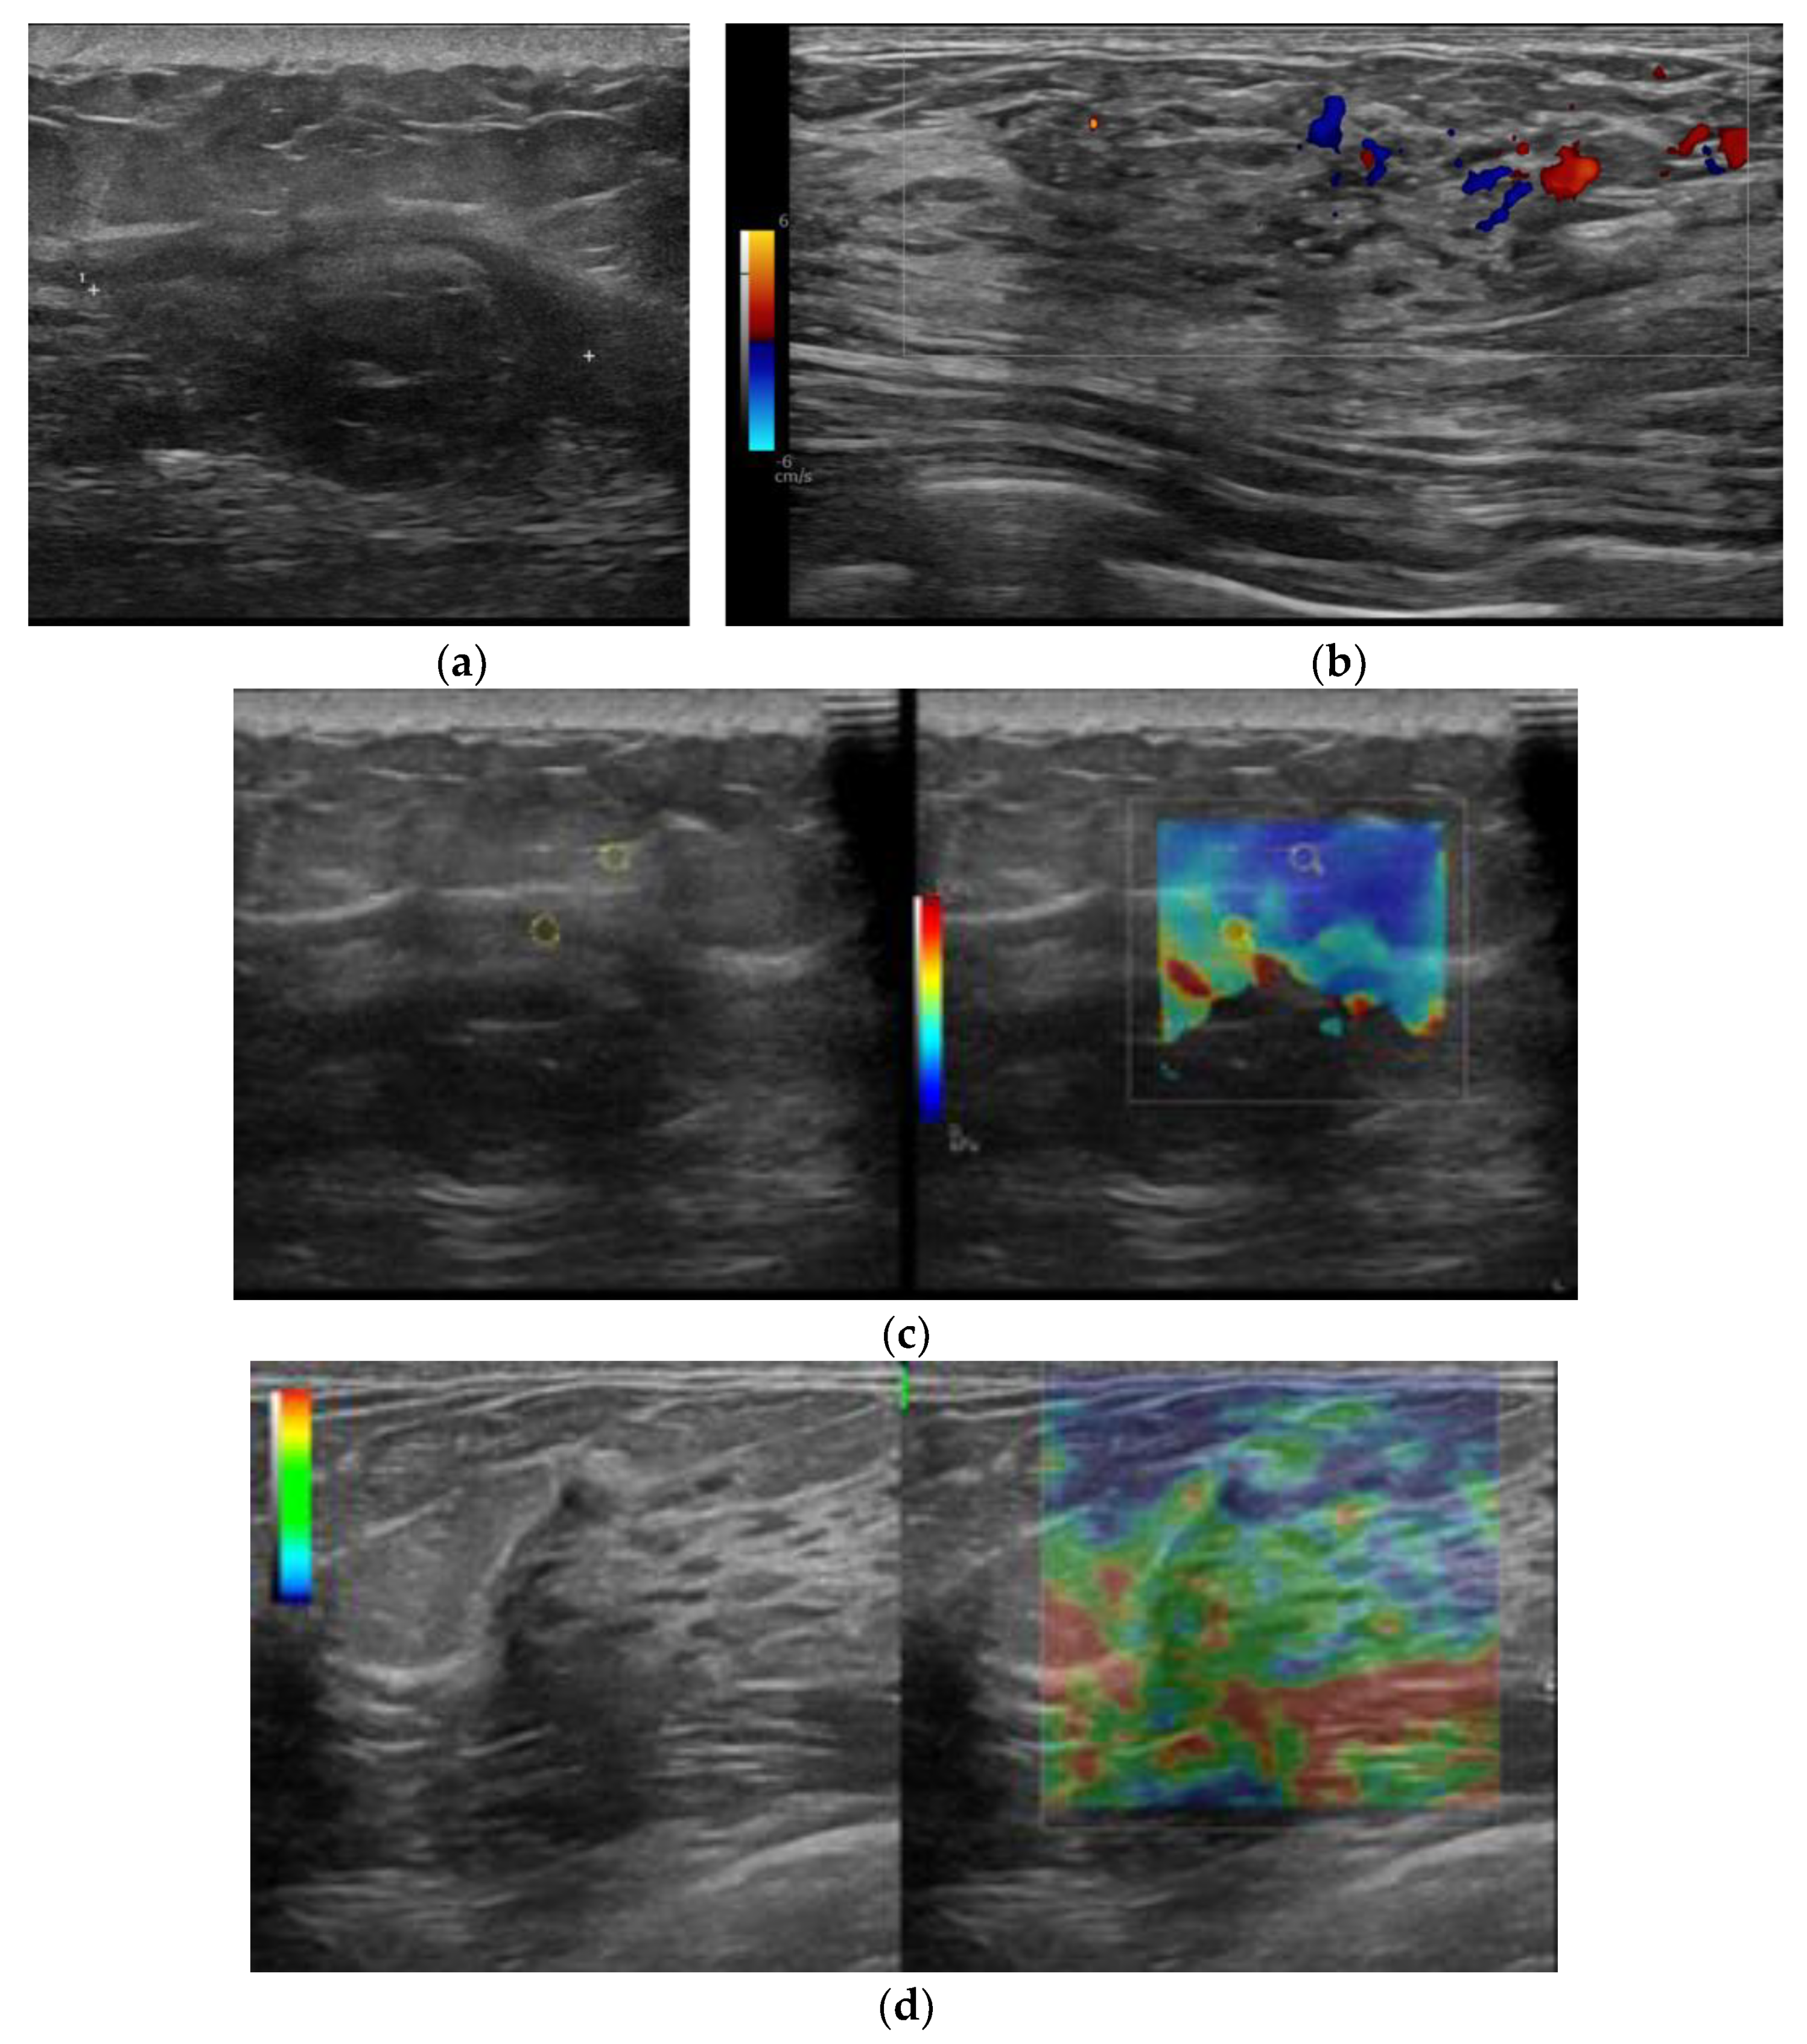

This module serves as the base as it analyzes US breast scans, systematically identifying their class based on several visual attributes. In this paper, we considered four types of US scans (i.e., B-mode, Doppler elastography, strain elastography, and shear-wave elastography). Examples of them are shown in Figure 3. Each type of scan has unique visual attributes that are specific to that type. For instance, in SWE-mode images, distinct characteristics emerged. Notably, the presence of a color bar with accompanying legends denoting units in kilopascals (kPa) and large colored contours were observed. SE-mode images also exhibited notable traits, with an absence of kPa unit indicators along the color legend bar, showcasing similarly large contours as observed in SWE-mode images. Conversely, Doppler images were distinguished by relatively smaller colored contour regions in comparison with SE-mode and SWE-mode images. Additionally, a notable feature was the presence of colored regions of interest (ROIs) that did not conform to a rectangular or square shape commonly found in SE-mode and SWE-mode images. These observations collectively aided the naked-eye identification and differentiation of visual attributes across different types of elastography images.

Figure 3. Four types of breast US scans images: (a) B-mode; (b) Doppler elastography; (c) shear-wave elastography; (d) strain elastography.